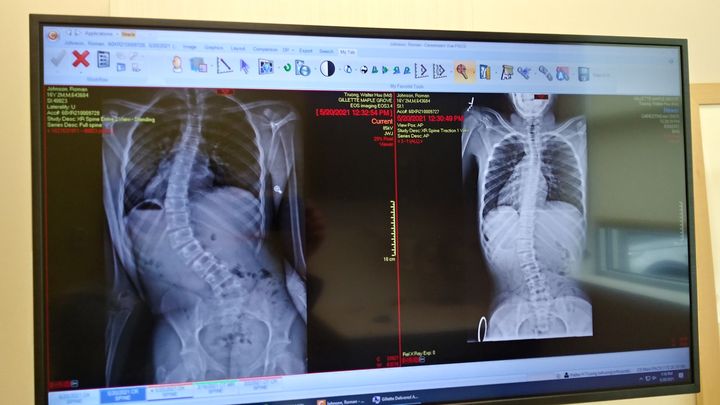

Proud single mother who has an amazing 16 year old son that was recently diagnosed with Scoliosis and is needs immediate Idiopathic Surgery before organ failure onsets. We have an amazing surgeon at Gillette's Children's Hospital and spinal surgery is taking place on June 14th 2021. There will be a 3-4 day stay at the hospital and 4 weeks post surgery he will have to have 4-6 weeks of rehabilitation therapy 2 times a week. They are inserting a rod from right below his neck to right above his pelvic bone. Many prayers and well wishes are so much appreciated! Thank you in advance for anything you are able to contribute, I am very modest in my ask and will not know fully out of pocket it will end up being. An important message is he .. Is going to have an Iron Man back. (His fav Marvel Hero)